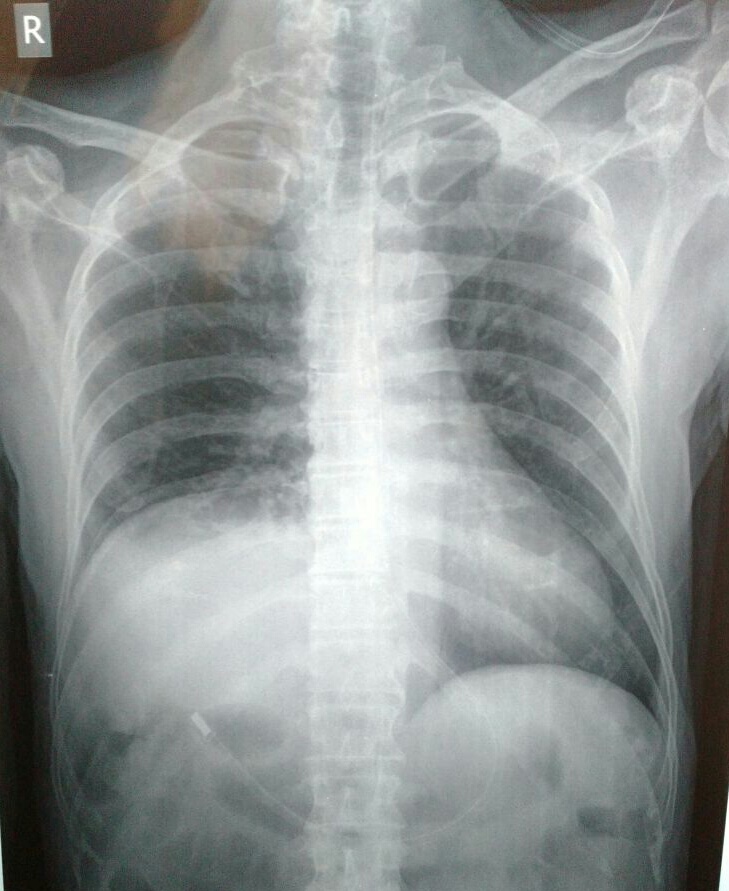

Chest film showing a left diaphragmatic paralysis. Download What Is Diaphragmatic Paralysis Diaphragmatic paralyses encompass a spectrum of diseases involving a single leaflet, known as unilateral. The diaphragm is a muscle that separates the chest and abdominal cavities. Depending on the severity of the paralysis and whether it is. Diaphragmatic paralysis is a condition characterized by the impaired function of the diaphragm, leading to respiratory. Paralysis of this muscle is uncommon. Diaphragm. What Is Diaphragmatic Paralysis.